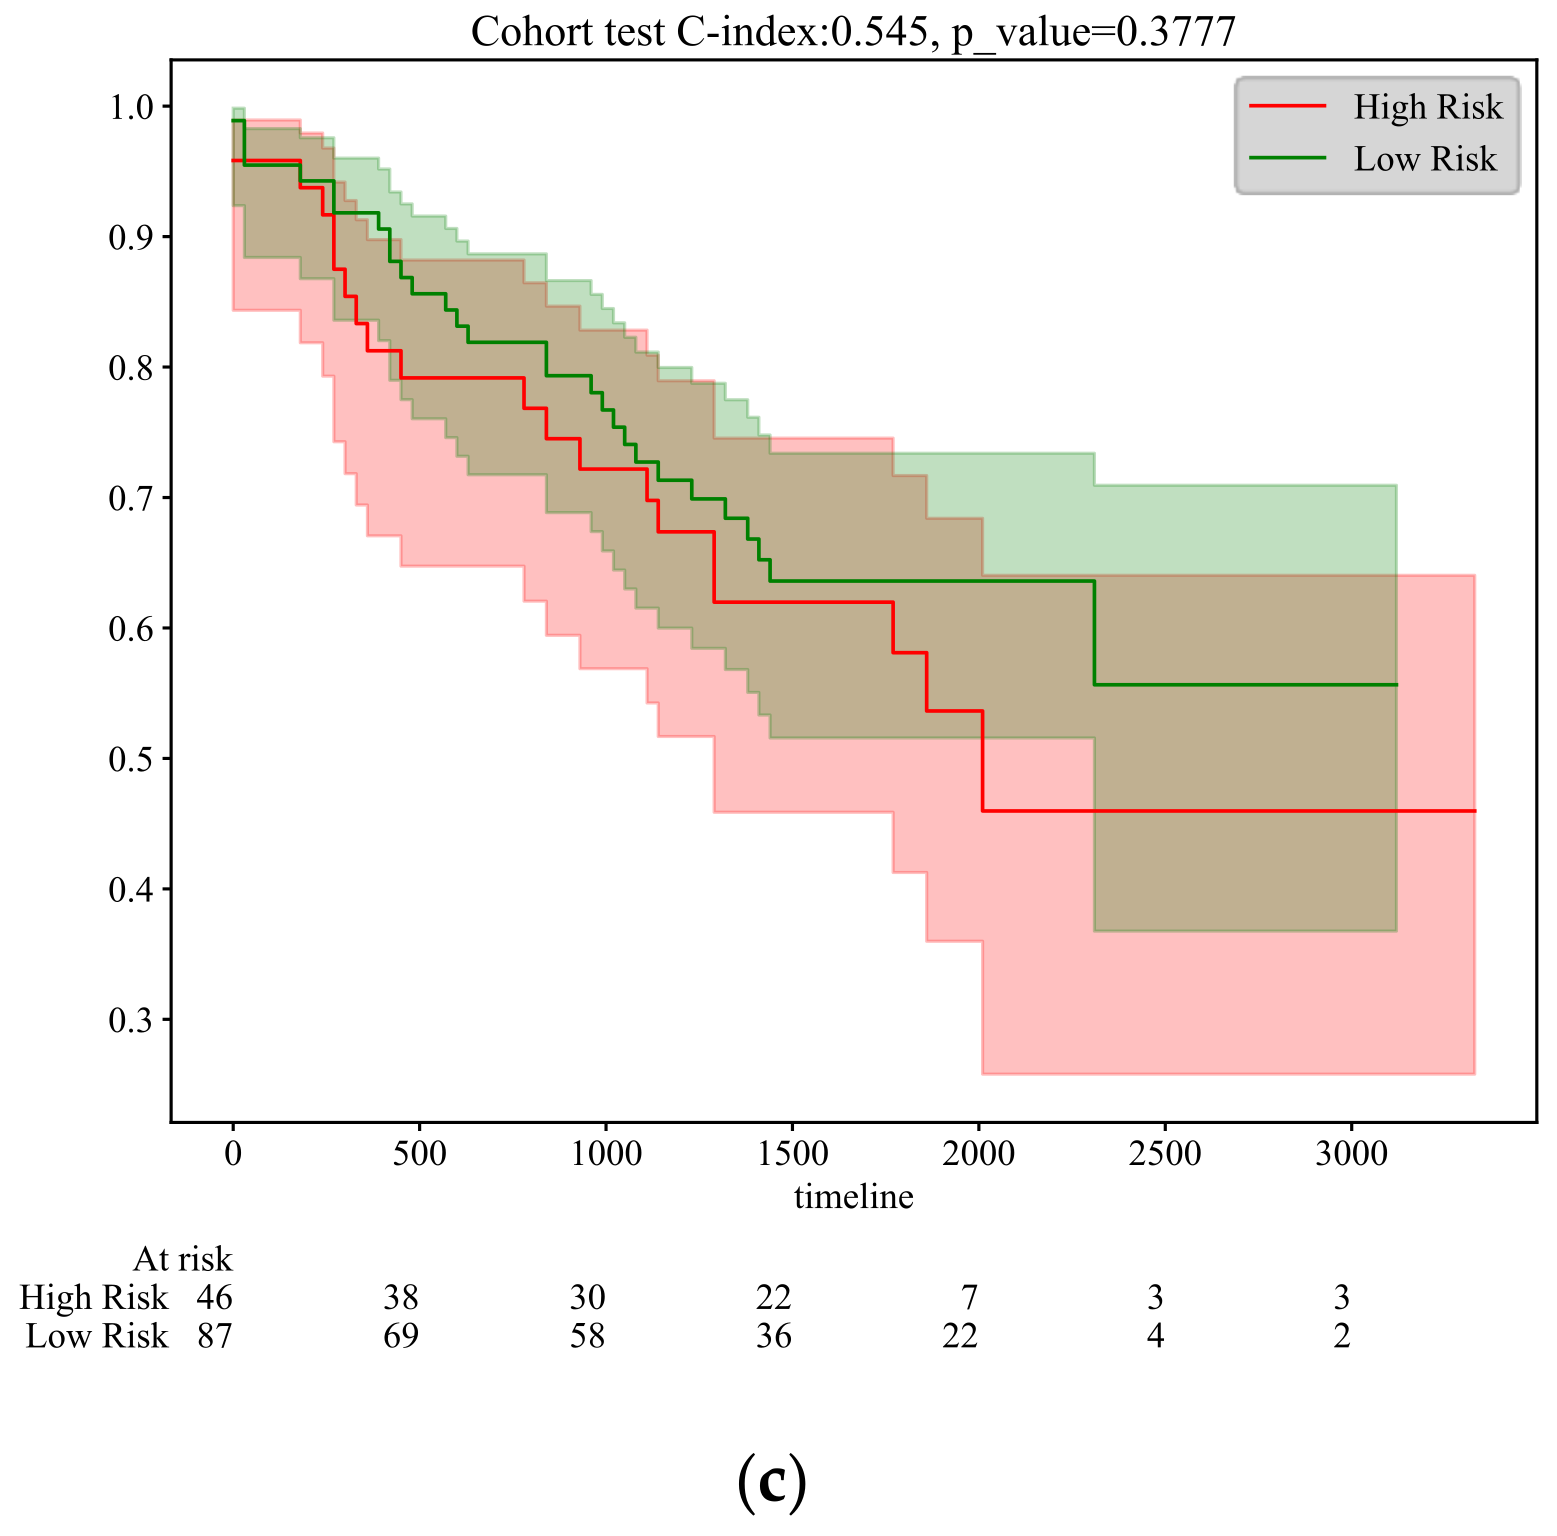

5.1. N Stage Prediction and Survival Analysis

5.2. Survival Time Prediction